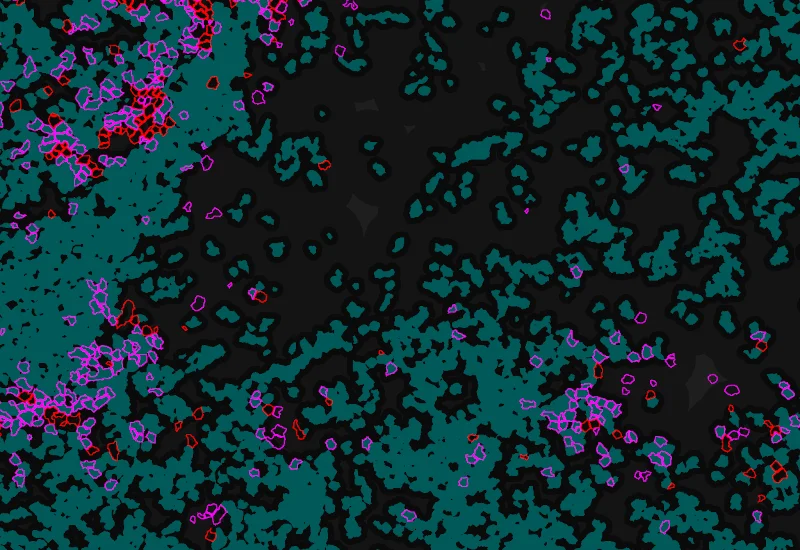

Phenotype 1 and Phenotype 2 detection

Phenotype 1 to 2 proximity 0-5μm

Phenotype 1 to 2 proximity 5-25μm

Phenotype 1 to 2 direct contact